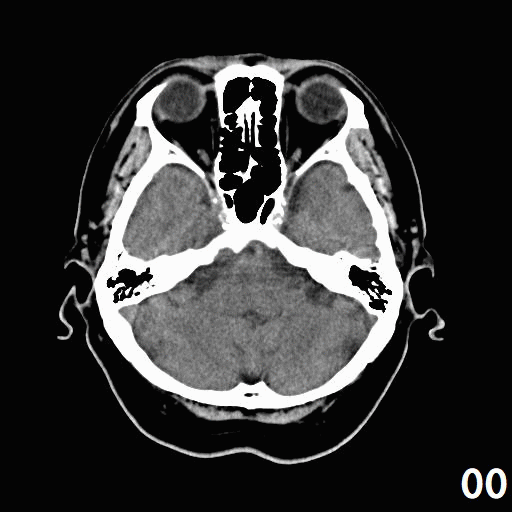

で、頭部のCT画像ファィルを、Gif-Aniを作った。

そのアニメは、 ここです。

朝から、妻に連れられて「人間ドック」へ。

オプションのCTを3種類も頼んだので・・・「ン」万円アップ。

「画像データをくれるかと聞いて、くれたら受ける」といったので、「発注」しました。

一部は紙データ、他はCDで渡すということで、頼みました。

1,2週間で送られてくるそうです。